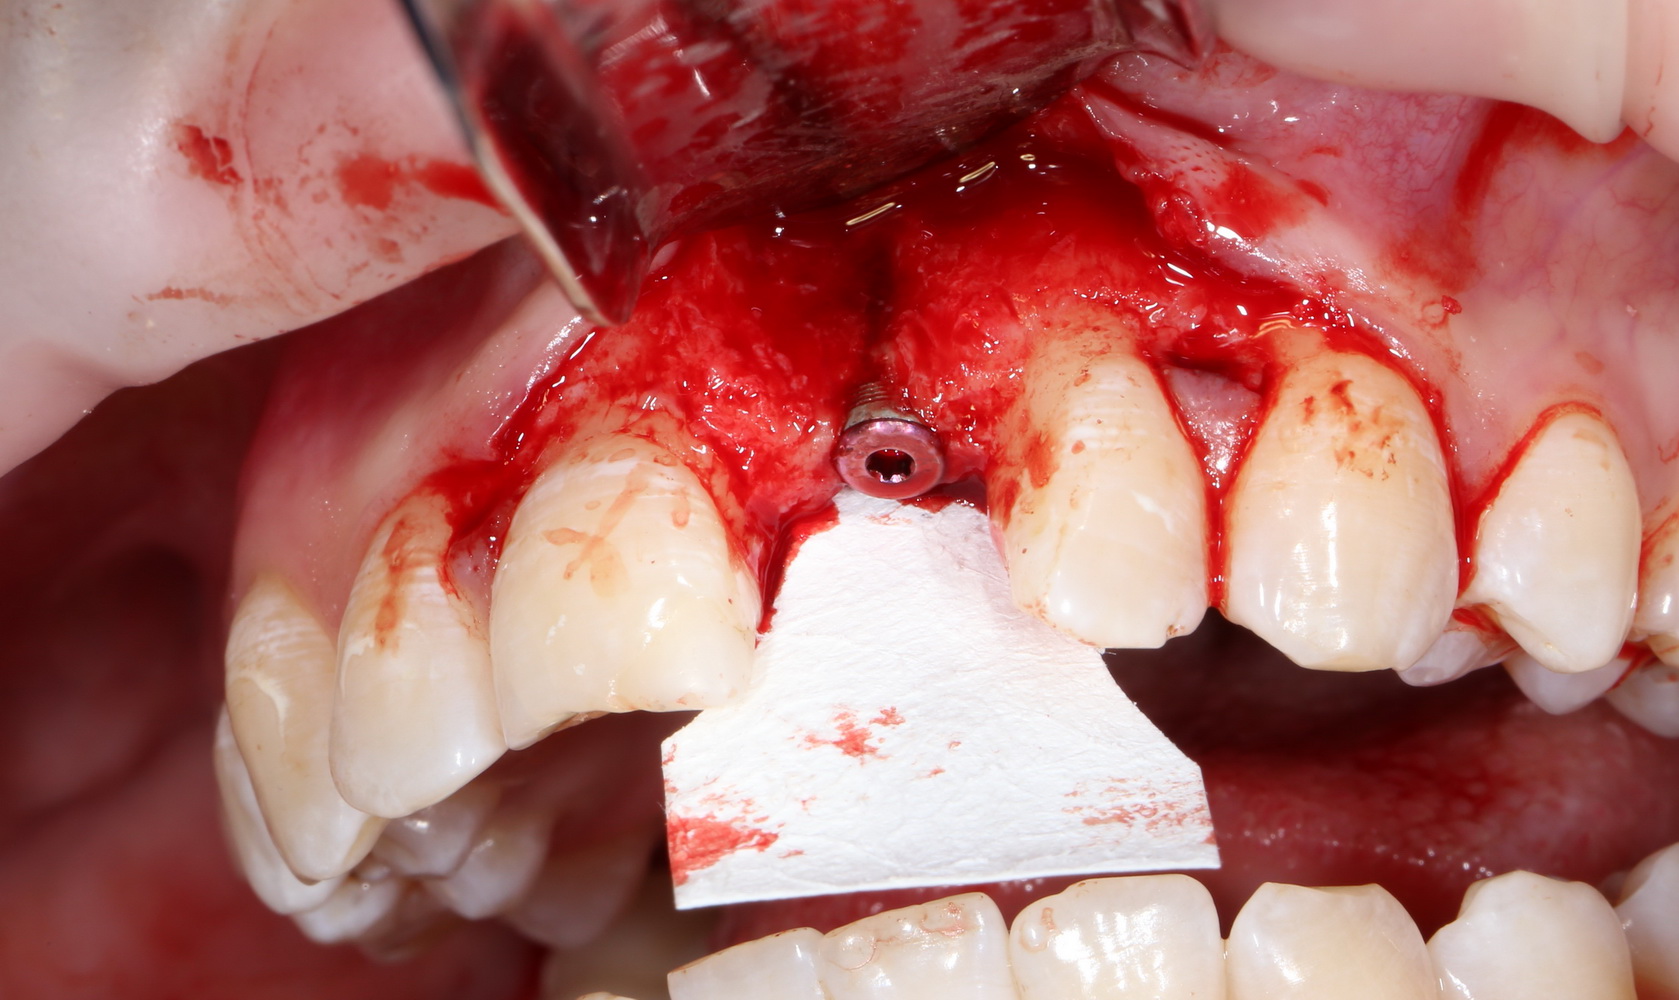

Лунка готова, устанавливаем имплантат:

Это Nobel Replace CC 3.5×13 mm. Оптимальный размер импланта для работы в этом клиническом случае.

Продолжим нашу работу. Имплантат установлен:

Работа закончена? Отнюдь, нет. Теперь наша задача — восстановить утраченные объемы костной ткани вокруг импланта. Ибо, как вы видите на фото, его вестибулярная поверхность, практически, просвечивает. И, если ничего не делать, дальше будет только хуже.